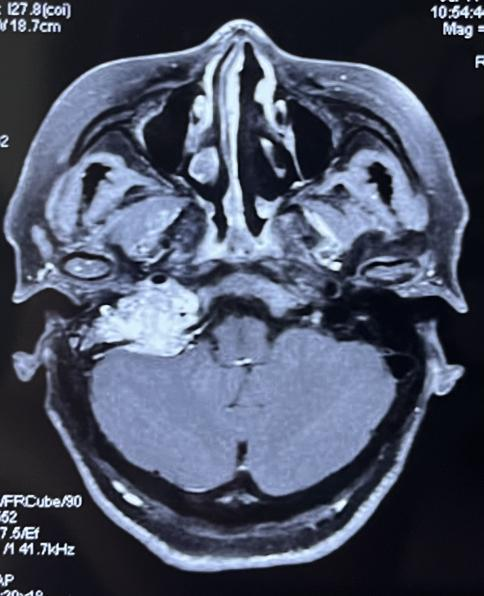

颈静脉孔区为侧颅底解剖最复杂的区域,该区域手术极其复杂,难度系数大,手术风险高。患者术前检查示右侧颈静脉孔可见不规则团块,等T1稍长T2信号影,大小约35mm*28mm*30mm,病变边界不清,内见多发迂曲血管,临近软脑膜可见明显强化(图1、2)。因肿瘤范围大,手术难度及并发症发生率极高,因此该患者入院后进行全面评估,并在耳鼻咽喉头颈外科主任任晓勇教授主持下,进行全院MDT讨论,麻醉科吴刚教授,神经外科许刚教授,以及全体耳鼻喉科医生进行疑难病例讨论。最终确定采用颞下窝typeA入路行肿瘤切除,并行外耳道封闭术。

图1